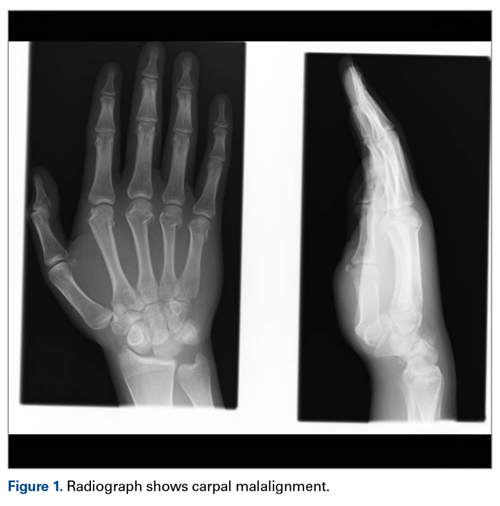

Later, however, the hand surgery team evaluated the radiograph as well as computed tomography (CT) scans and found a translunate, transradial, transtriquetral, transtrapezoid perilunate dislocation of the wrist with multiple metacarpal neck fractures ( Figures 1-5 ).The next day, with the patient under general anesthesia, an attempt to reduce the perilunate dislocation by manipulation was unsuccessful. Open reduction and internal fixation (ORIF) were performed through a dorsal approach; the perilunate dislocation was reduced and stabilized with lunocapitate 1.2-mm Kirschner wire (K-wire). The scapholunate and lunotriquetral ligaments were found to be intact, and the significantly displaced triquetral fracture was treated with internal fixation involving 2 minifragment screws ( Figure 6 ).

Our patient’s associated multiple metacarpal neck fractures can be explained by the peculiar double-impact injury with initial axial loading across the hyperextended metacarpophalangeal joint, followed by axial loading across the hyperextended and ulnar-deviated wrist, causing greater arc perilunate fracture-dislocation. The mechanism of lunate injury in this case seems to be longitudinal impaction of the capitate shearing against the volar lunate in the axial plane causing a volar lip fracture (Teisen type I), and this may be accentuated by tension in the volar radiolunate ligament. 6,7 Associated triquetral fracture in perilunate dislocation is well described in the literature. 6 However, the trapezoid fracture in our case implies a very atypical pattern of force transmission with the arc probably passing more distally through the trapezoid laterally and the triquetrum medially.